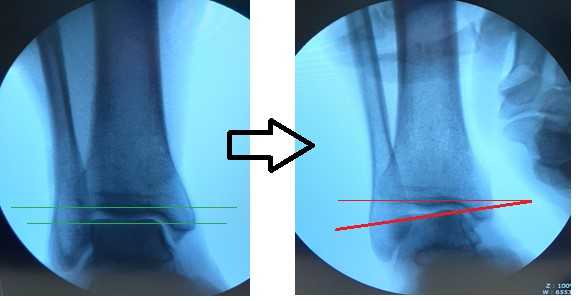

Для подтверждения механической нестабильности выполнены стресс-рентгенограммы голеностопного сустава с «варус-стресс тестом» и «тестом переднего выдвижного ящика». Критериями для постановки диагноза нестабильности является ангуляция таранной кости в коронарной плоскости более 4 градусов и смещение таранной кости кпереди в сагиттальной плоскости на 4 мм, или разница с контрлатеральной стороной в 2 градуса и 2 мм соответственно.

Если с варус-стресс тестом всё очень наглядно, оценивать передний выдвижной ящик рентгенологически чуть сложнее. Для этого можно либо обозначить центр купола таранной кости и встречной суставной поверхности большеберцовой кости точками и сравнивать расстояние между ними с или без нагрузки в задне-переднем направлении, либо использовать в качестве вспомогательного ориентира тень медиальной лодыжки и расстояние от неё до начала шейки таранной кости.

При выполнении стресс рентгенограмм определяется выраженная латеральная нестабильность голеностопного сустава.